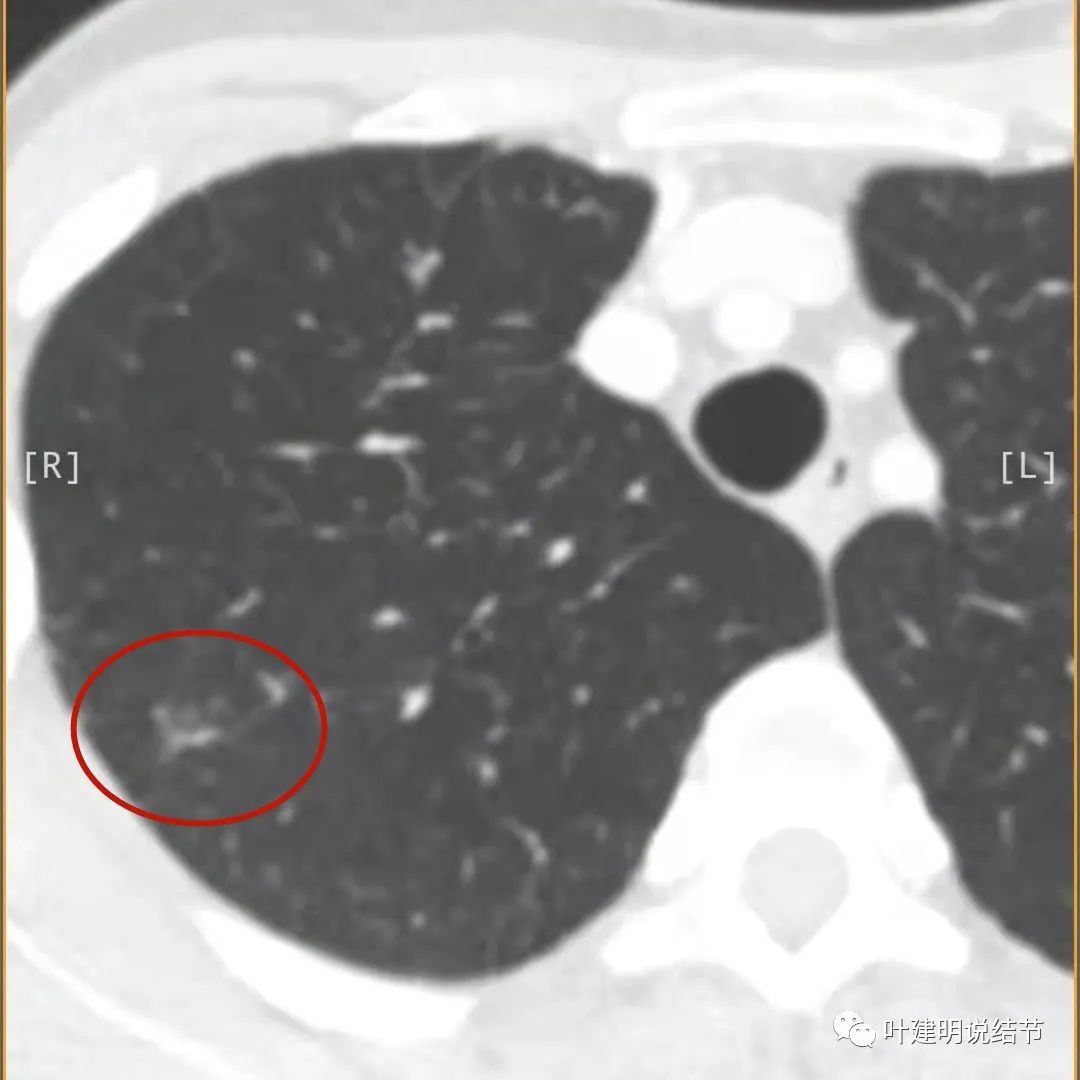

我们再来看薄层的CT图像:

病灶出现,模糊的磨玻璃影

部分密度过高,且呈条状

邻近胸膜有增厚(蓝色箭头),主病灶边界较清(红色箭头),实性部分密度过高(粉色箭头),旁边有磨玻璃影,散且模糊(砖色箭头)

邻近胸膜有增厚(蓝色箭头),主病灶实性部分密度过高(粉色箭头),旁边有磨玻璃影,散且模糊(砖色箭头)

邻近胸膜有增厚(蓝色箭头),主病灶实性部分密度过高(粉色箭头),旁边有磨玻璃影,散且模糊(砖色箭头),病灶有空腔(黄色箭头)

主病灶边界较清(红色箭头),实性部分密度过高(粉色箭头),病灶边缘向内凹,缺乏膨胀性(桔色箭头),病灶有空腔(黄色箭头)

邻近胸膜有增厚(蓝色箭头),主病灶的壁密度过高且整个壁密度都高(粉色箭头),旁边有磨玻璃影,散且模糊(砖色箭头)。内壁不均质(此不舒服)

邻近胸膜有增厚(蓝色箭头),主病灶囊壁密度过高(粉色箭头),内部有突起(细红色箭头),旁边有磨玻璃影,散且模糊(砖色箭头),中间有空腔,内壁有些区域又是光滑的

邻近有卫星灶(绿色箭头),主病灶密度过高(粉色箭头),旁边有磨玻璃影,散且模糊(砖色箭头)

邻近胸膜有增厚(蓝色箭头),主病灶边缘较为平直,缺乏膨胀性(桔色箭头),实性部分密度过高(粉色箭头),旁边有磨玻璃影,散且模糊(砖色箭头)

病灶边缘较为平直,膨胀性不足(桔色箭头)

胸膜增厚突起明显,与主病灶可能不相连

这是较上面的层面,有卫星灶(绿色箭头)以及淡磨玻璃影,散且淡,胸膜增厚突起(蓝色箭头)

病灶以胸膜处增厚为主,与空腔性病灶不相连,此为慢性炎病灶

胸膜明显增增厚

胸膜明显增厚,又出现与胸膜不相连的病灶,密度过高,边缘模糊,中间密度很高密度(粉色箭头所指),边缘平直无膨胀(桔色箭头)

胸膜增厚